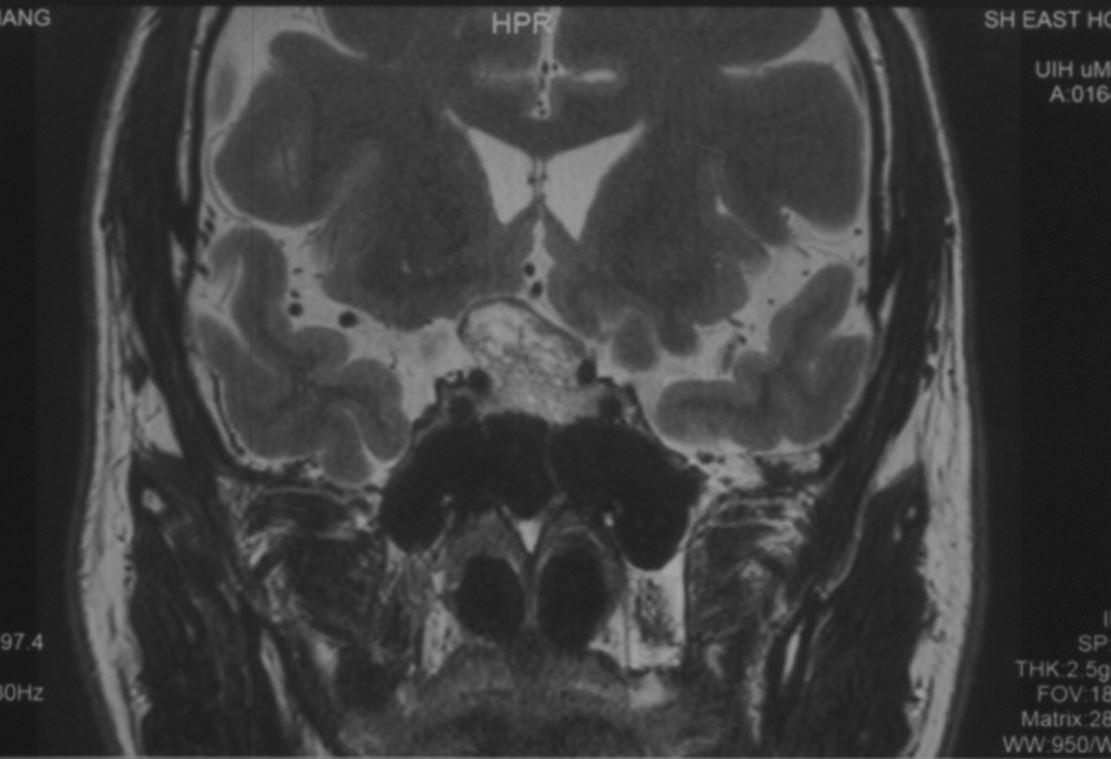

患者为中年患者,因头痛伴视物模糊半年起来就诊,鞍区增强MRI示:鞍区占位性病变,肿瘤大小约2.5cm,肿瘤突破鞍隔向上生长,顶部偏向右侧,视交叉受压明显,两侧侵犯海绵窦。T1WI为等信号,T2WI为混杂等信号,明显强化。复旦大学附属肿瘤医院神经外科高阳

术前磁共振图像: